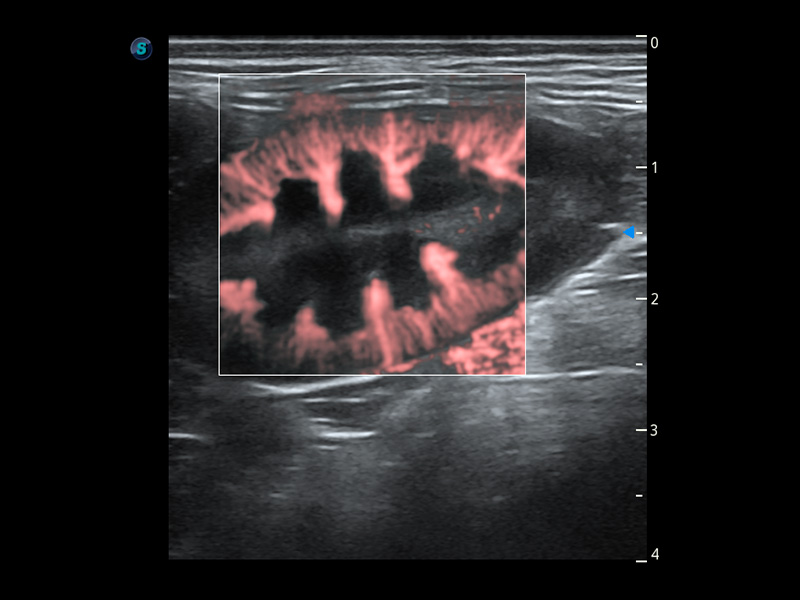

ProPet 60 作为一款高端台式动物超声设备,为动物医生的日常诊断提供了一系列贴合动物临床需求、解决临床实际问题的高级成像功能。凭借全系列高清探头,满足医生对腹部、心脏、生殖、浅表、肌骨等成像的所有需求,切实帮助您提升检查效率,提高诊断信心。

动物是人类最亲密的朋友和最值得信赖的伙伴。球速体育入口也一直致力于探索动物专用的超声影像解决方案。 全新推出的ProPet系列,是球速体育入口在动物超声影像智能化、专业化、精准化的一次跨越式革新。动物不能用言语来表述自己的不适,通过超声影像,ProPet系列搭建了动物医生与不同物种沟通的“桥梁”,为动物医生注入了“治愈之力”。